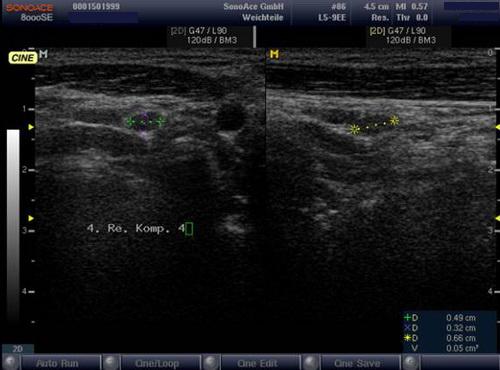

Sonografie: Sonographisch 3 suspekte Lymphknoten cervical rechts.

Sonografie: Kein Korrelat des Verdachts einer zervikalen Lymphknotenmetastase.